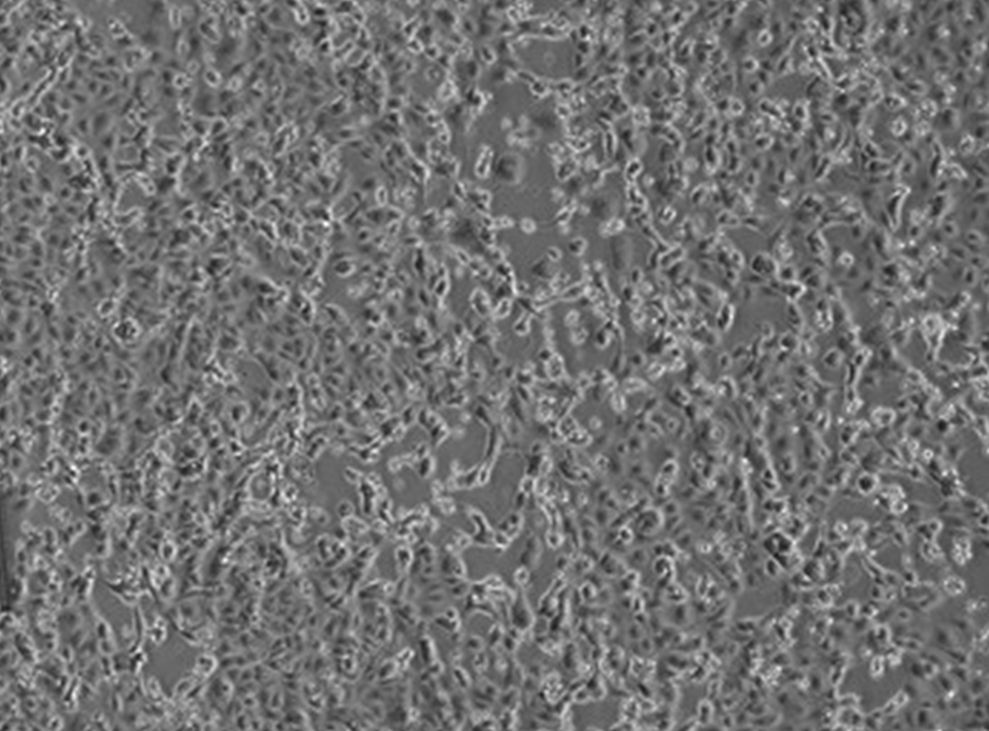

MILANO (ITALPRESS) – “Un 38enne italiano e’ risultato positivo al test del coronavirus. Sono in corso le controanalisi a cura dell’Istituto Superiore di Sanita’. L’uomo e’ ricoverato in terapia intensiva all’ospedale di Codogno (Lodi) i cui accessi al Pronto soccorso e le cui attivita’ programmate, a livello cautelativo, sono attualmente interrotte. Le persone che sono state a contatto con il paziente sono in fase di individuazione e sottoposte a controlli specifici e alle misure necessarie”. Lo comunica in una nota l’assessore al Welfare della Regione Lombardia Giulio Gallera.